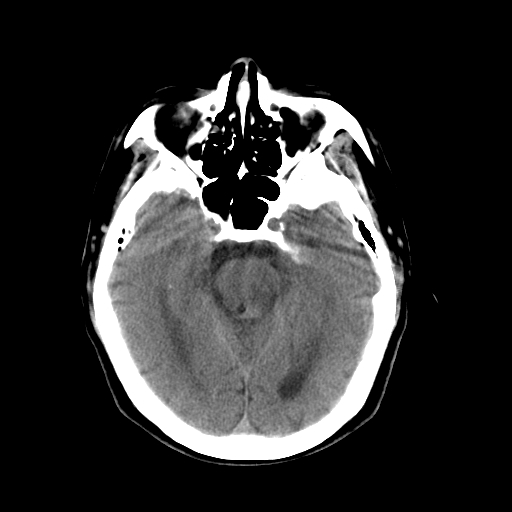

以下是引用dsl555在2008-11-11 18:52:00的发言:[br]四脑室后上方,四叠体池上方可见一小结节状稍高等密度影,比40天略大,建议mri或增强

以下是引用zjzjr在2008-11-12 8:28:00的发言:[br]四脑室后方略高密度影,周围环一低密度水肿带,四脑室受压变形,考虑小脑蚓部血肿吸收期或占位,建议增强